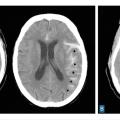

Le scanner doit être réalisé en urgence. Il montre une hyperdensité des espaces sous-arachnoïdiens, évalue la sévérité par l’échelle de Fisher et recherche les complications précoces (fig. 1 et tableau 1).

Si l’IRM est accessible et que l’état du patient est compatible, les séquences FLAIR, T2* ou imagerie pondérée en susceptibilité magnétique (SWI) peuvent remplacer le scanner cérébral sans injection (fig. 2), avec une sensibilité plus élevée pour le diagnostic d’hémorragie méningée.